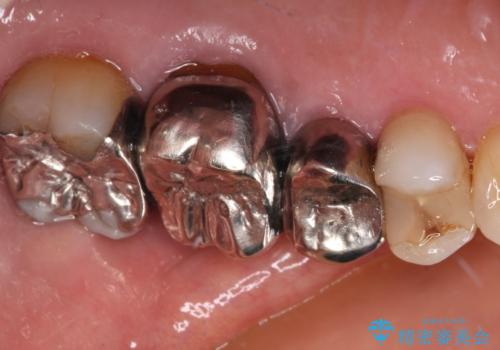

虫歯の範囲が大きく、部分的な詰め物では対応が難しいため、オールセラミッククラウンにて補綴することとしました。

また虫歯除去の際に、万一根管と交通してしまっても根管に感染を起こさないために、ラバーダム防湿をして虫歯除去しました。